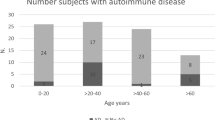

Analysis of risk factors for WMH severity in CD patients by Fazekas scale

We used the Fazekas classification method to divide the CD patients into 3 groups according to the WMH grade by univariate analyses (Table 3) and correlation analysis (with significant difference, Table 4). The CD patients with moderate to severe WMH were older and had a longer disease course, higher blood glucose and TG levels, higher frequency of diabetes, LVH and arrhythmia than the patients in the other categories. WMH severity in CD patients positively correlated with age (r = 0.532, P = 0.000), disease course (r = 0.257, P = 0.009), fasting blood glucose(r = 0.212, P = 0.033), postprandial glucose (r = 0.278, P = 0.005), frequency of diabetes (r = 0.245, P = 0.013), LVH (r = 0.398, P = 0.001) and hypothyroidism (r = 0.246, P = 0.014).

The markers of cortical and subcortical atrophy: SFR (r = 0.197, P = 0.049), BFR (r = 0.200, P = 0.044), BCR (r = 0.278, P = 0.005) and third ventricle width (r = 0.242, P = 0.015) were positively associated with the progression of WMH in the CD patients.